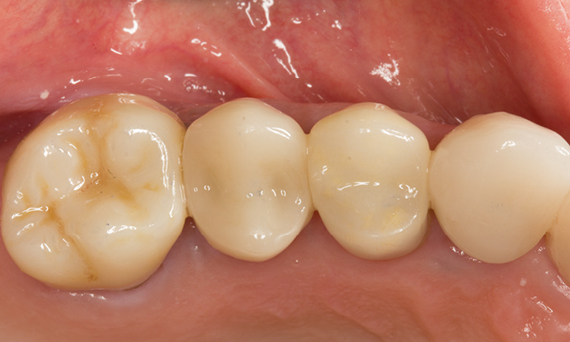

Quadrant rehabilitation

Two CEREC Tessera crowns and two inlays

Within a single visit of four hours the restoration of two crowns and two inlays, which were 15 years old, was carried out. The patient was very pleased with the very good esthetic result.

Before: Insufficient fillings in the second quadrant. The restorations were about 15 years old.

After: Chairside-fabricated crowns made from CEREC Tessera (teeth 26/27). Inlays for teeth 24 and 25 made of composite blocks.